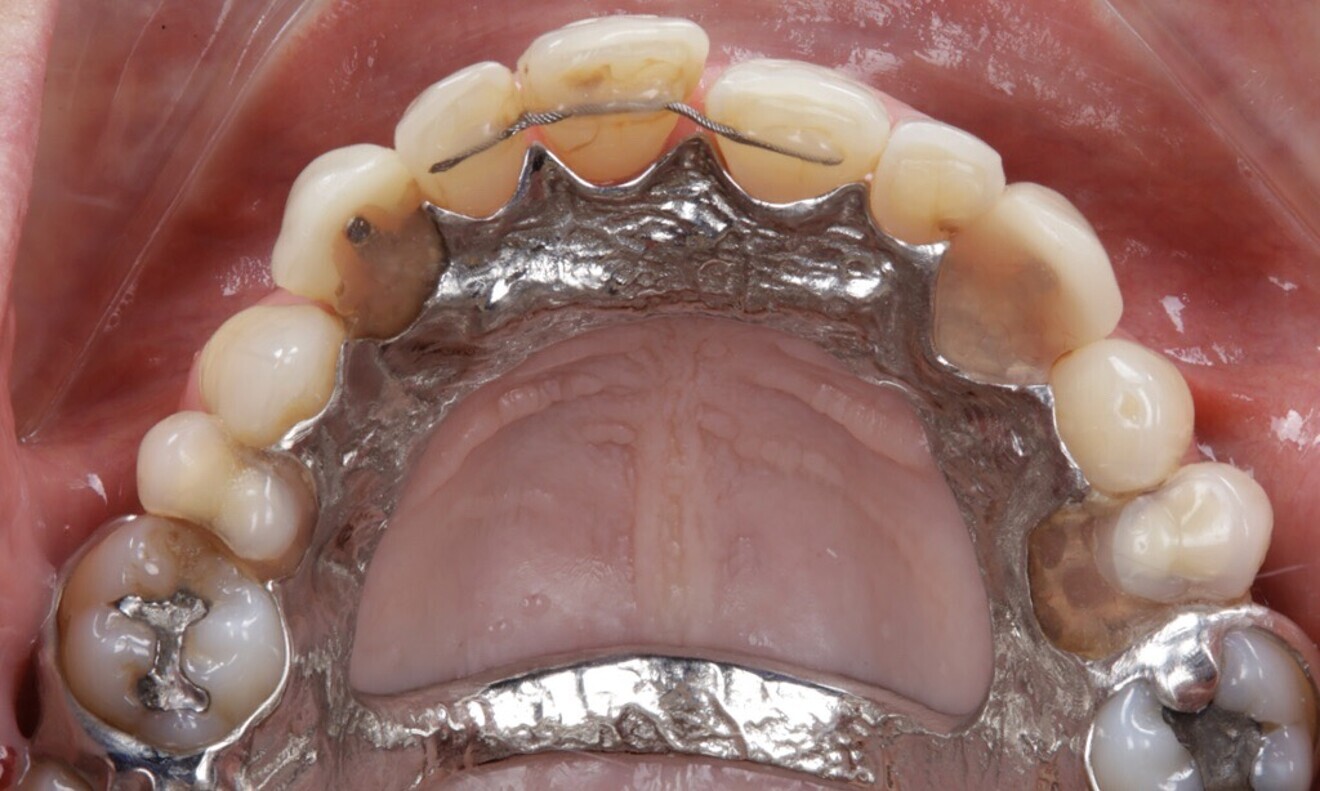

The patient wore a removable restoration in the maxillary arch and presented with anterior retainers in both the maxillary and mandibular arches owing to tooth mobility caused by periodontal disease. Teeth #15, 13, 23, 25, 27, 36, 35, 44, 45, 46 and 47 were missing. Additionally, the patient presented with several dental fillings (Figs. 4–7).

Figs. 4–7: The intra-oral examination showed generalised periodontitis, a removable maxillary restoration and multiple missing mandibular and maxillary teeth.